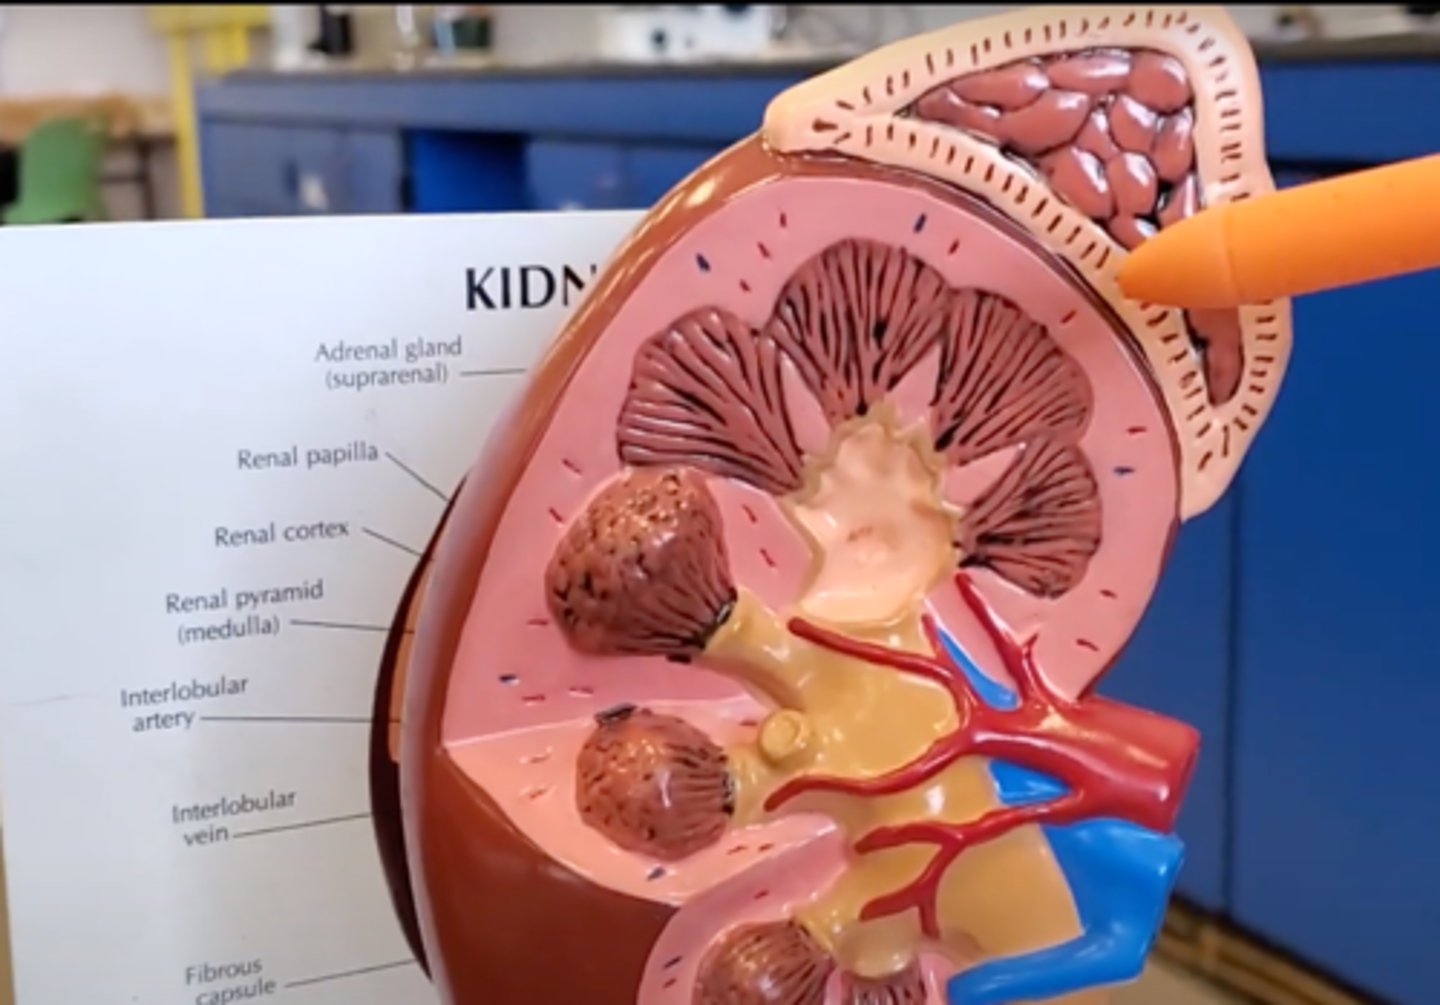

renal pyramid

2

renal column

3

cortex

outer layer of the kidney

ureter

A duct leading from the kidney to the urinary bladder.

nephron

the functional unit of the kidney

Adrenal gland

A pair of endocrine glands that sit just above the kidneys and secrete hormones that help arouse the body in times of stress.